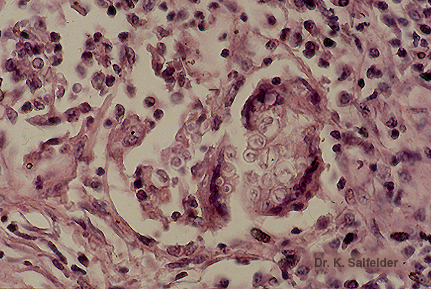

Abb. 14,13: Lobomykose

Gelegentlich findet sich eine Riesenzellen-Reaktion. HE-Faerbung